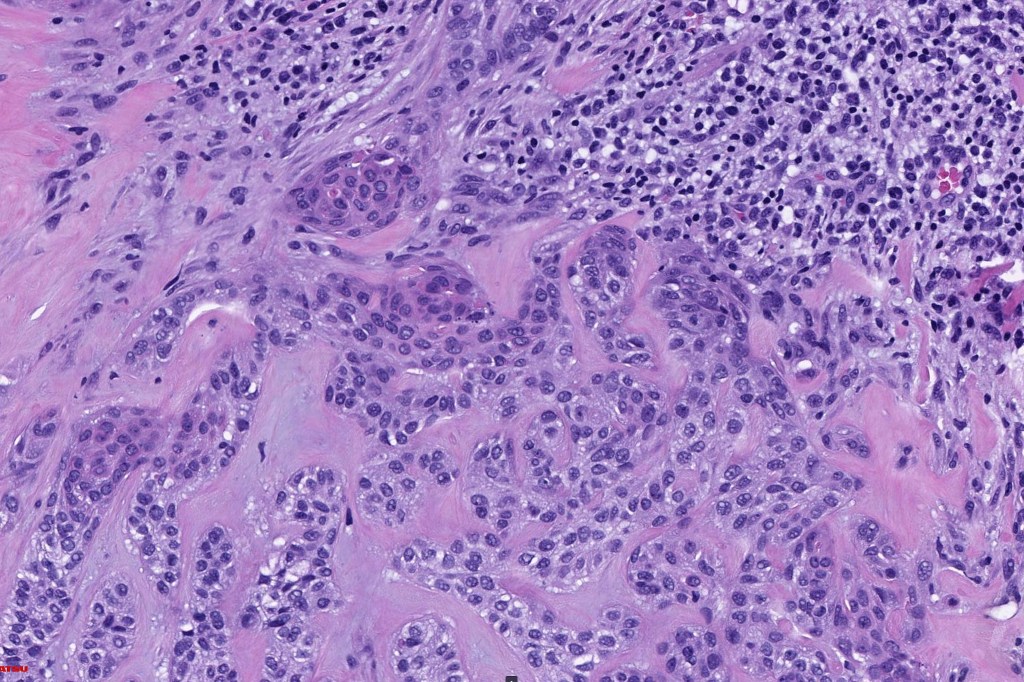

Histological features

•Typical trichilemmoma surrounding a densely, hyalinized collagenous region containing narrow epithelial strands sometimes mimicking a carcinoma

•The stroma contains glycogen & acid mucopolysaccharides & is DPAS+ve

•Stromal component is rich in type 1 collagen

The diagnosis of both these tumors is nearly always readily apparent. The desmoplasia can result in suspicion of malignancy by the unwary. Trichilemmoma can be distinguished from poroma by the hyalinized thick basement membrane and absence of ducts. Desmoplastic trichilemmoma is distinguished from squamous carcinoma by the presence of typical trichilemmoma at the periphery and from trichilemmal carcinoma by the absence of pleomorphism & significant mitotic activity. Trichilemmal carcinoma does not show a pre-existent trichilemmoma. CD34 expression excludes squamous carcinoma